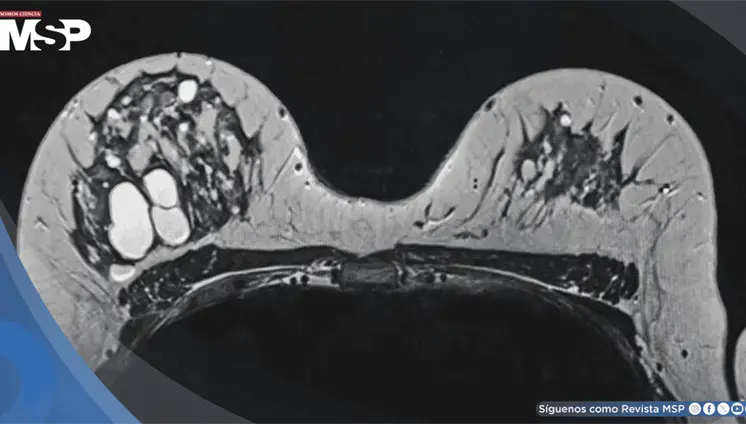

Lo que comenzó como un cuadro frecuente de dolor pélvico y dismenorrea en una mujer, terminó siendo un carcinoma folicular originado en estruma ovárico maligno. La paciente tenía solo 35 años, marcadores tumorales completamente normales y ninguna alteración tiroidea.